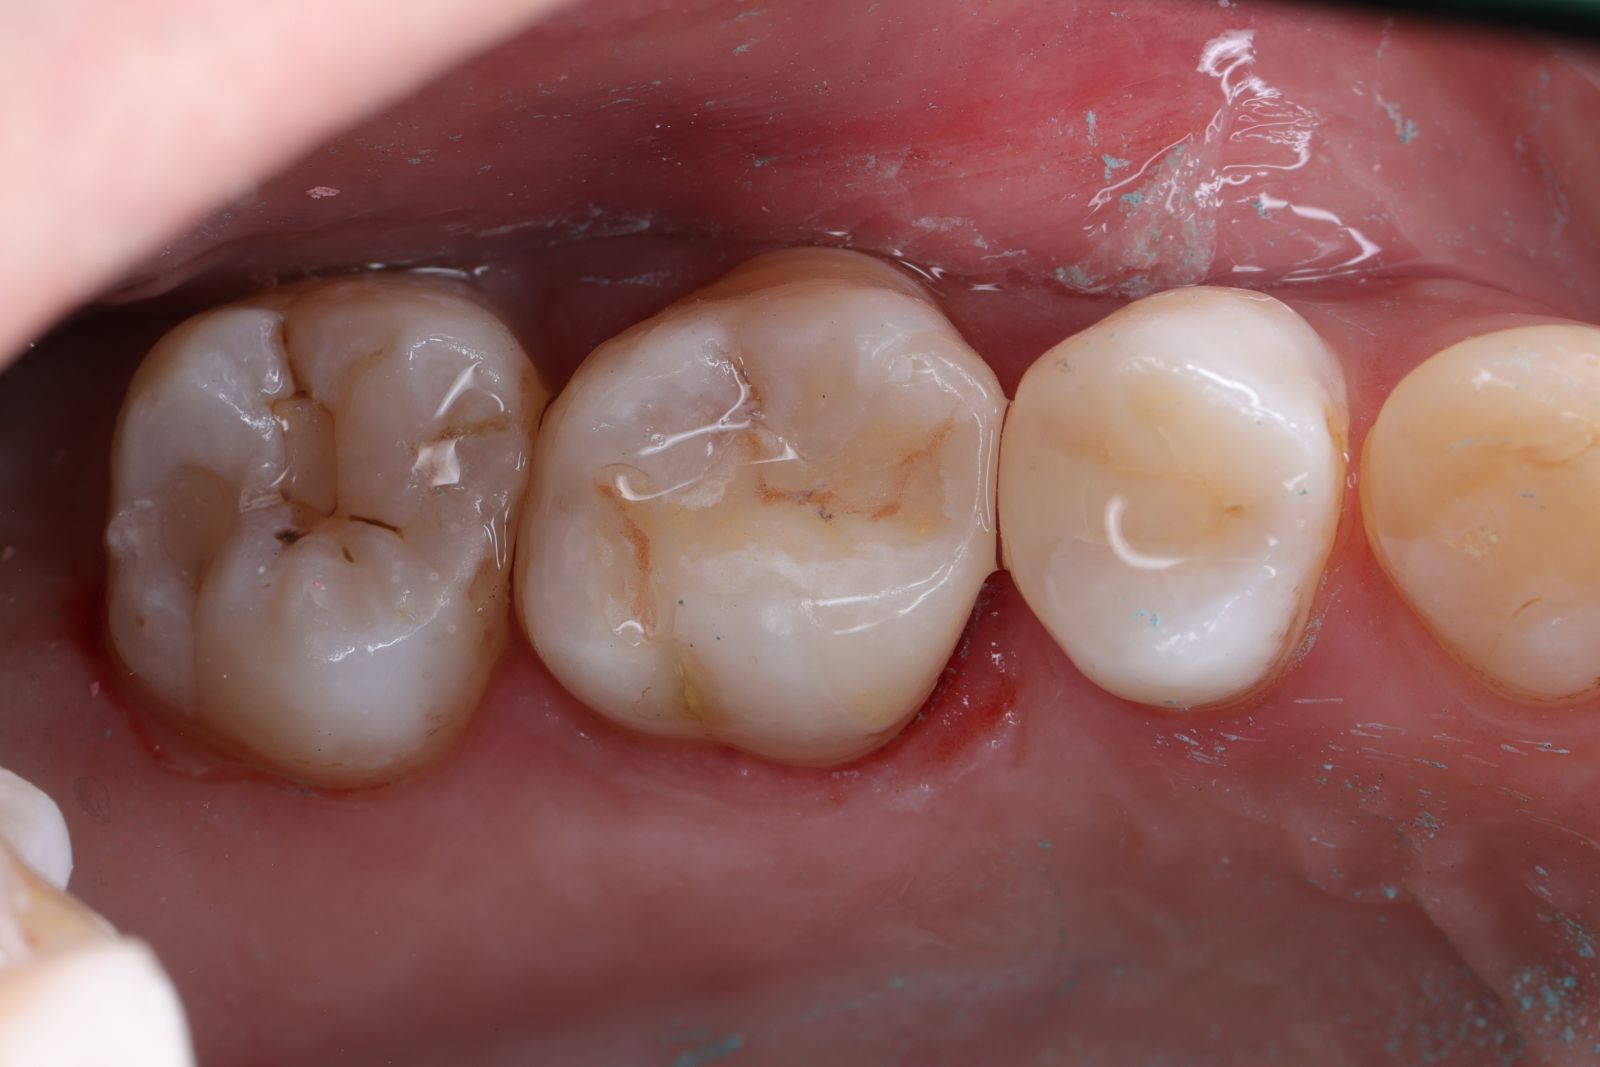

【 案 例 二 】